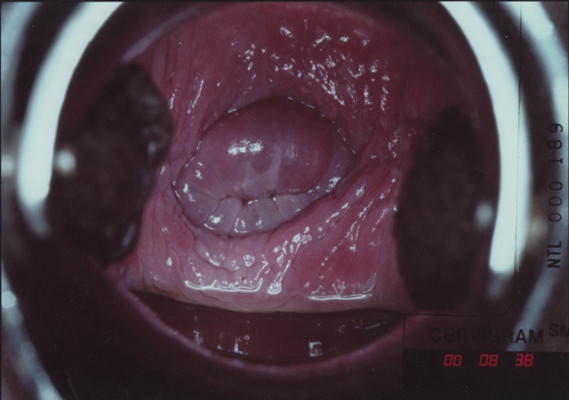

子宮頸癌圖片

宮頸癌

宮頸癌

宮頸癌

宮頸癌

宮頸癌

宮頸癌

宮頸癌

宮頸癌

宮頸癌

宮頸癌

宮頸癌

宮頸癌

宮頸癌

宮頸癌

宮頸癌

宮頸癌

宮頸癌

宮頸癌

宮頸癌

宮頸癌